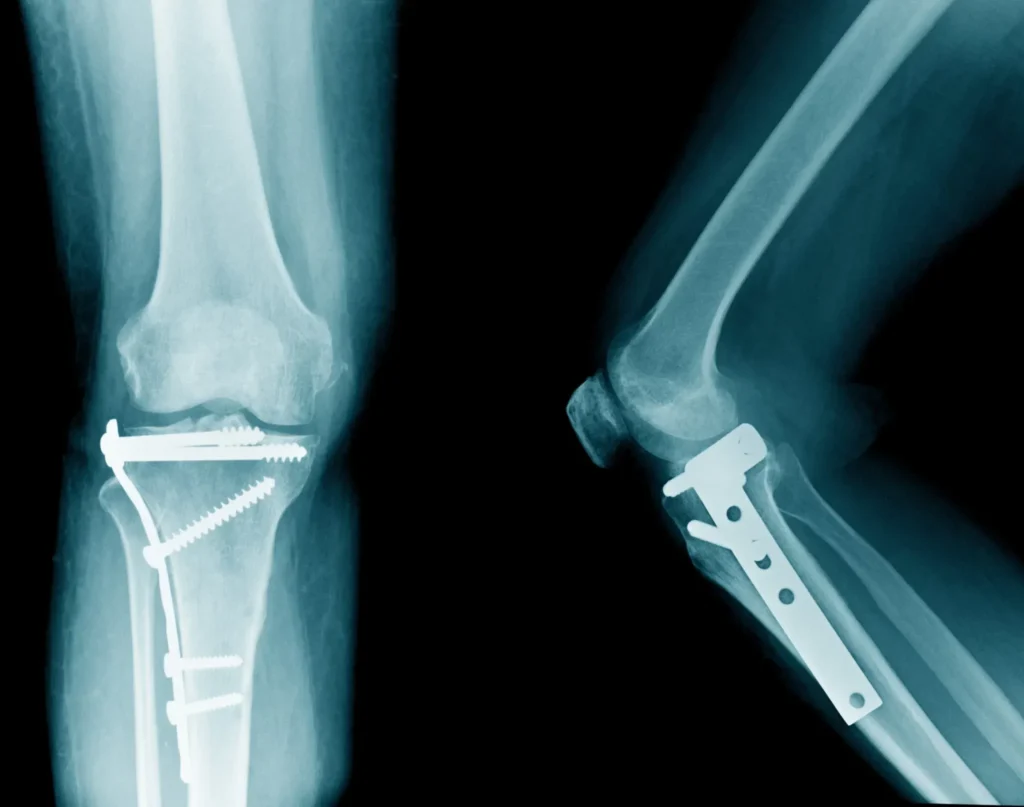

Leg fractures are one of the most common and serious leg injuries. These injuries typically occur due to high-impact accidents like car crashes. simple breaks to compound fractures where the bone pierces the skin.

The knee is a highly complex joint, vulnerable to injuries such as torn ligaments (ACL, MCL), dislocations, and meniscus tears. These injuries often occur in car accidents, falls, or sports-related incidents

Severe fractures, ligament tears, or joint damage may require surgery to restore stability or mobility. Recovery varies based on injury and procedure.